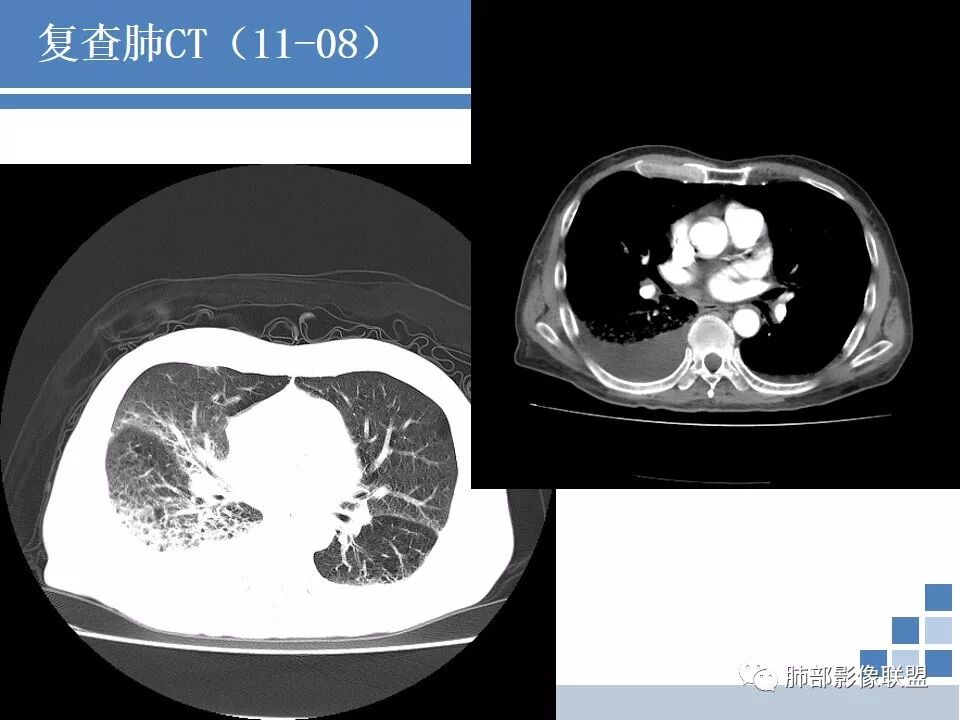

临床:发热咳嗽一周,血沉、CRP高,低氧血症,结核伽马干扰素阳性。抗生素治疗无效;

CT:肺气肿肺大泡背景,右上肺磨玻璃及实变影,10天及20天复查影像明显进展至两肺更大范围,伴右侧胸水。

晨读病例:双肺野透光度增强,胸膜下可见肺大泡。右肺上叶病灶三次影像对比病灶增大增多并出现空洞,液平。左肺上叶出现淡片状影,边缘模糊。右侧胸腔积液。考虑感染性病变,结核合并感染。

肺气肿,肺大泡背景,一周前出现症状,右肺上叶网格状及条片状病变,渗出为主。抗炎一周复查,范围加大,右侧胸水增多。再次复查,左肺上叶尖后段亦出现高密度影。增强扫描右上肺病变实性部分似乎没有强化。结合临床实验室检查,考虑结核可能性大。

晨读:老年人,咳嗽、咳痰伴发热1周。中性比、白介素6、血沉、CRP、PCT高,低氧血症,结核伽马干扰素阳性,肿标多项阳性。广谱抗生素治疗无效。CT:刀鞘样气管,肺气肿肺大泡背景,右上、下肺大片实变影伴蜂窝,进展快,沿胸膜下分布,有重力分布趋势,胸膜阻隔,10天及20天影像快速进展至两肺更大范围,伴右侧胸水,左上肺也出现病灶。常规考虑:感染性病变,结核?低蛋白明显,奴卡不除外。鉴别:肺炎型肺Ca。

如果没有结果,分析是这样:这个人肺气肿基础,出现大片实变,那符合气肿性肺炎,头两次影像上还看不出结核来,但是白细胞不高,中性粒仅仅高一点的,然后血沉高,R干扰素高,抗感染不好。然后这个人有老年痴呆,初期可能会考虑这个人会不会只是一个细菌性肺炎呢,进展快。入院常规给与抗细菌没有问题。但是到11.08号影像出现一些端倪。一般气肿性肺炎虽然说可能好的不那么快,但是给与了亚胺培南这么高级的药反而进展,再加上血常规和一些实验室检查,好像普通细菌感染就有一点说不过去了。到第三次,出现空洞了,和肺气肿肺炎的气肿已经不一样了,气肿随着实变增加,里面应该会填实才对,但是出现空洞,这个说明不再是气肿里面的,而是真的空洞,而且还是那种肺尖的、光滑、有壁结节的空洞。